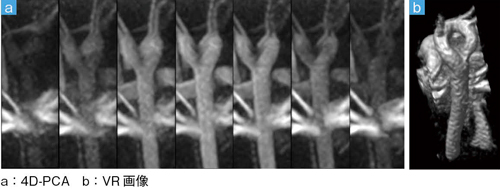

■症例2:重複大動脈弓(10歳,男児)の心臓MRA

■症例3:フォンタン手術術後(18歳,女性)の心臓MRA